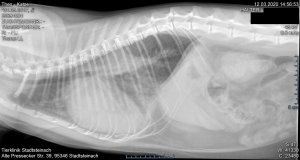

Kurze Zusammenfassung: Unser Kater Theo ist schwer Herzkrank (fortgeschrittenes

HCM) und hatte ein Lungenödem. Wir waren bei einem Tierarzt und haben ihn mehrmals auf die Schwere der Krankheit hingewiesen. Symptome: Seine

Bronchitis" zum Tierarzt fahren. Nach kurzer Rücksprache mit der behandelnden Kardiologin und der Notfallklinik verlangten wir ein Röntgen. Mittlerweile machte Theo Maulatmung... Weder wollte er das Röntgen machen, noch Theo ein zweites Mal ansehen. Er machte uns blöd an und schickte uns weg. 1 Stunde nach dem Arztbesuch lag Theo nur noch röchelnd am Boden und schrie nach jämmerlich nach Hilfe. Wir sind sofort in die Tierklinik wo sie im Röntgen feststellten dass der ganzen Körper mit Wasser zu gelaufen ist. Dort bekam er dann eine 3 tägige Therapie, die ihm half wieder stabil zu werden und normal atmen zu können. Hätten wir auf den Arzt gehört, wäre Theo an diesem Tag ziemlich sicher an dem Lungenödem gestorben.